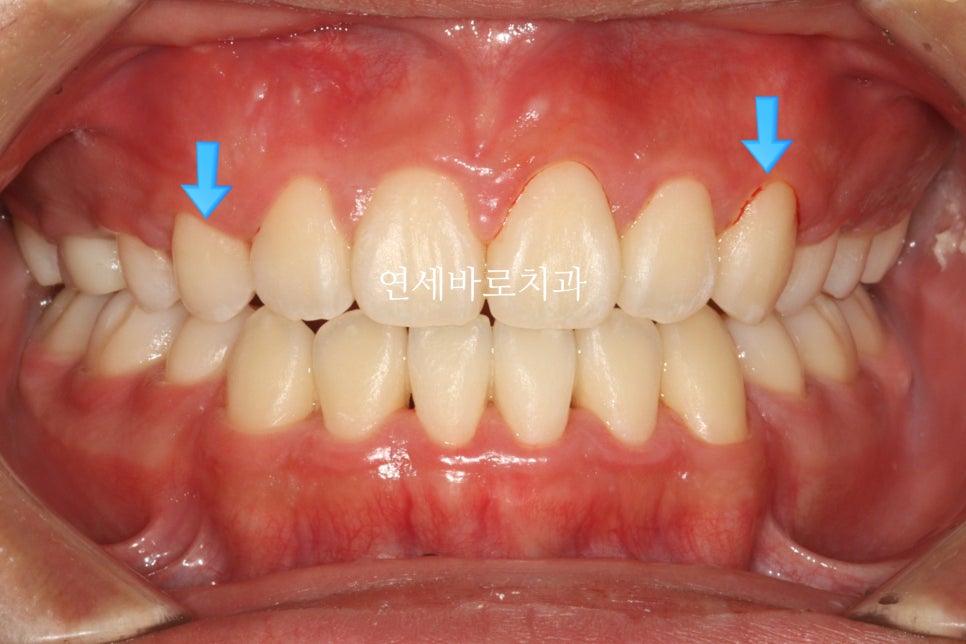

시작 전 모습입니다.

어머니도 아이가 매복치아가 있는지 전혀 모르고 있다가 우연히 교정상담하러 와서 발견한 경우입니다.

그 심미적 문제가 이것입니다.

화면의 왼쪽은 작은 어금니

오른쪽은 송곳니 입니다.

그래서 모양이 다르죠.

이런문제가 있긴 하지만 거의 티가 나진 않습니다.